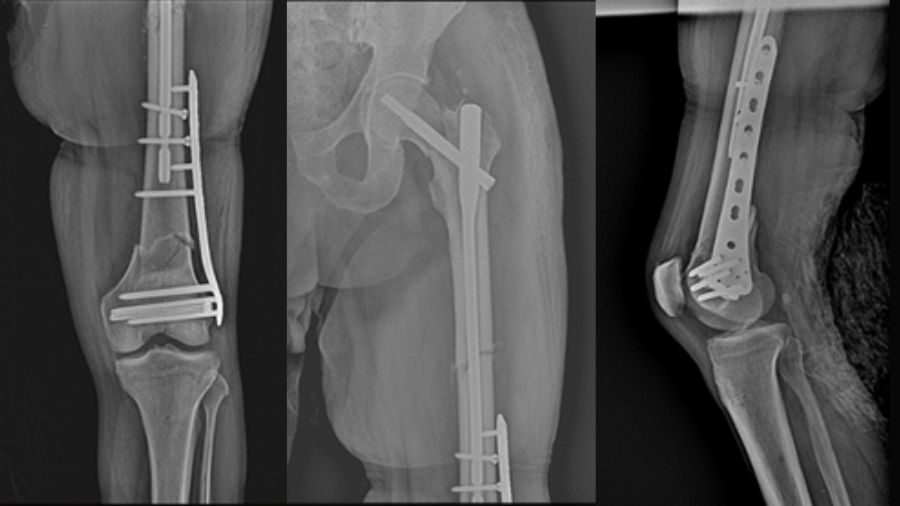

This case report describes a high-energy trifocal femoral fracture (intracapsular femoral neck, femoral shaft, and complete distal articular femur) treated with an intramedullary nail, free cannulated screws, and a LISS plate.

This combination of implants, not previously reported in the literature, allowed for an anatomical reduction with absolute stability of the distal periarticular fracture and a functional reduction with relative stability in the other two fractures (shaft and femoral neck).

As seen in the following images, all fracture sites healed with near-complete functional recovery, and no complications or deficits were reported. The full clinical case, including a video demonstrating the patient's functional recovery, can be accessed via this link.

We used an antegrade reconstruction nail for the femoral neck and diaphyseal fractures, cannulated screws for the distal intra-articular fracture, and a LISS plate for the supracondylar femur fracture. This combination prioritizes articular fractures with direct reductions and optimally treats the femoral shaft with intramedullary nailing.